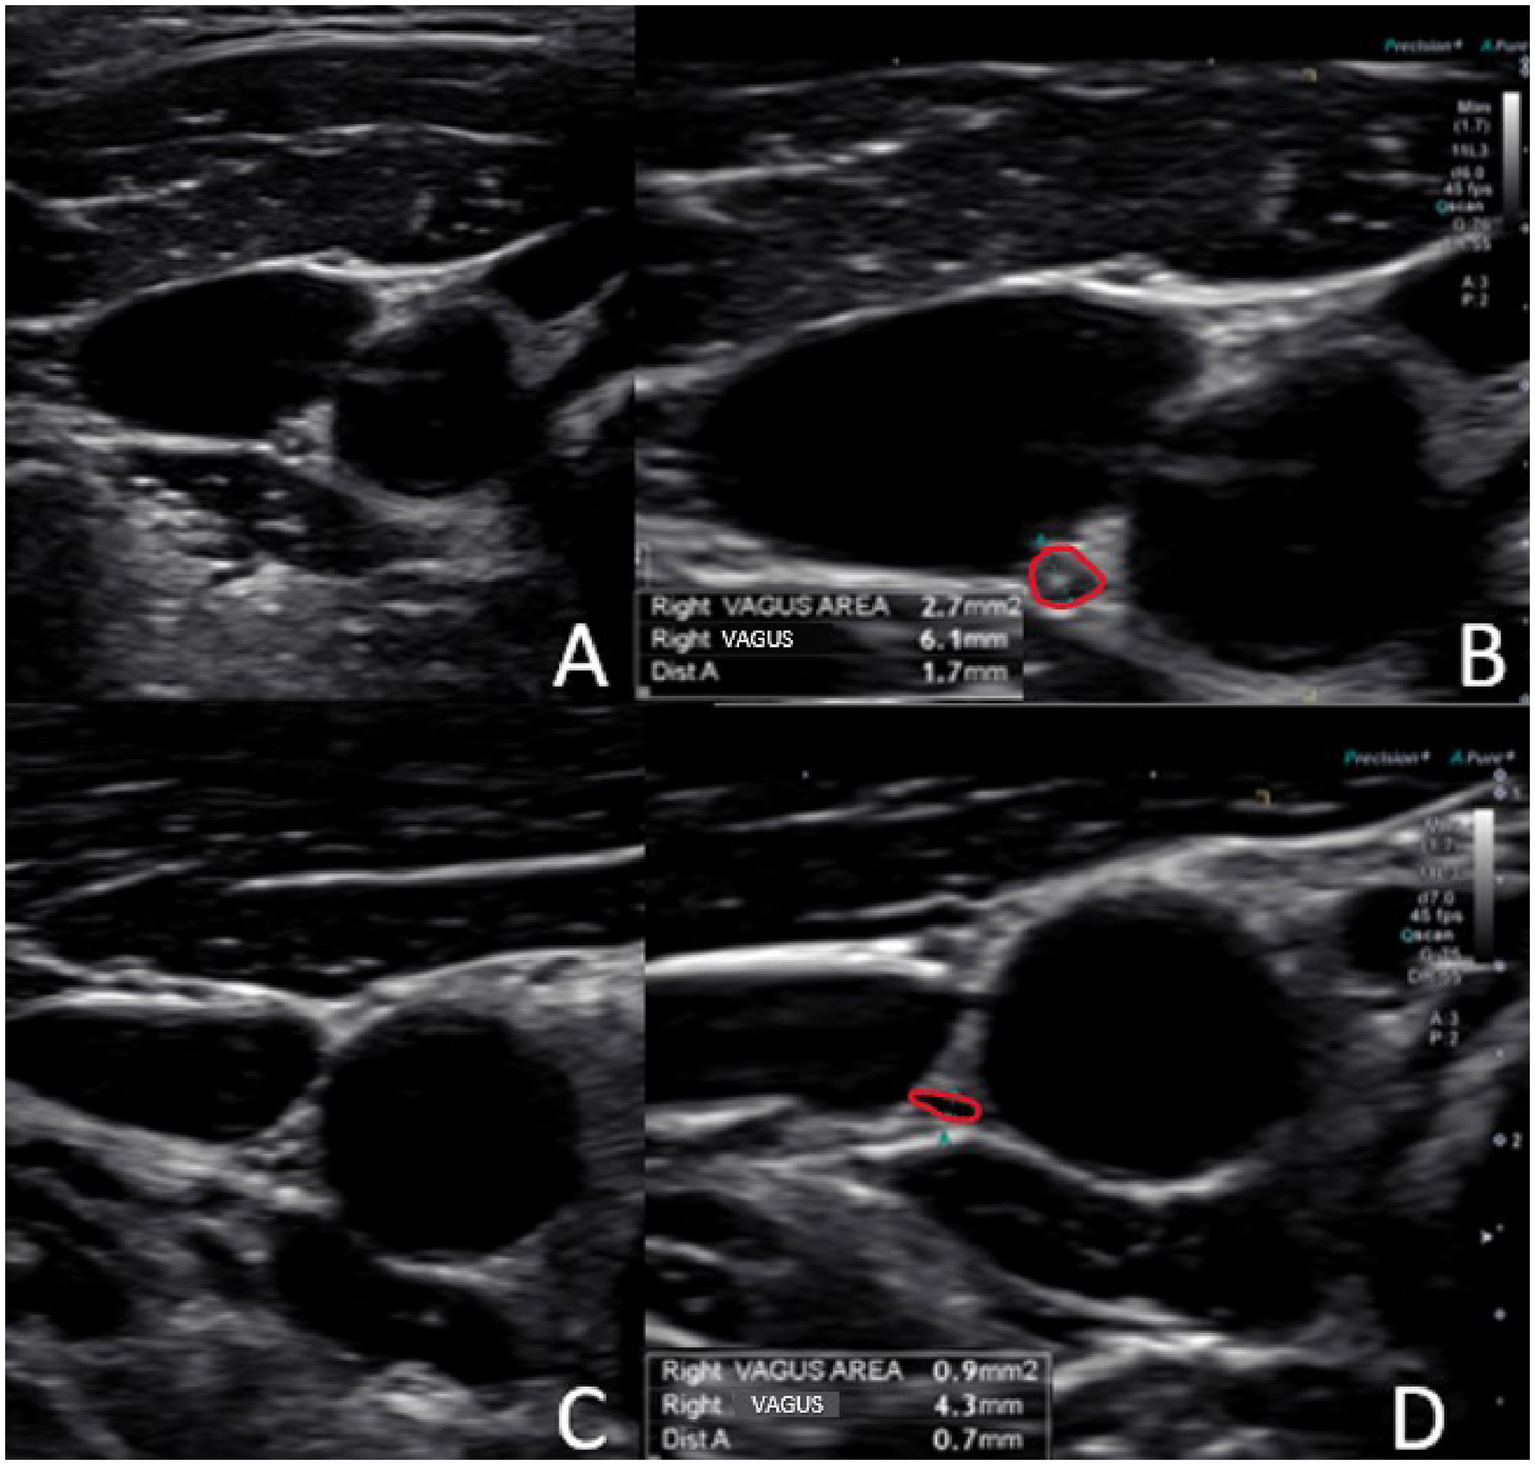

Using high-resolution ultrasound, the VN is easily examined, with the most common location of the nerve in the mid-neck lying posterior to the IJV and lateral to the carotid artery (54). The VN cross-sectional area can then be measured (see Figure 8). Normal cross-sectional areas are between 2 and 3 mm (2, 55–58). Studies have shown that the right VN is significantly larger than the left (59). Vagus nerve degeneration is documented by a decrease in the cross-sectional area on ultrasound in the mid-cervical region. The VN cross-sectional area has been shown to decrease with age, as well as with various diseases (up to 30%), including Parkinson’s disease, diabetes, alcoholic-induced dysautonomia, and amyotrophic lateral sclerosis, and can be correlated with symptomatology (60–63). Stretch and tension on the VN can be seen on ultrasound by changes in configuration at various cervical levels and with different head/neck positions (see Figure 9).

Figure 8

Ultrasound of the carotid sheath showing the vagus nerve. (A) Normal. (B) Normal image magnified and measured. (C) Degenerated vagus nerve. (D) Degenerated image magnified and measured.